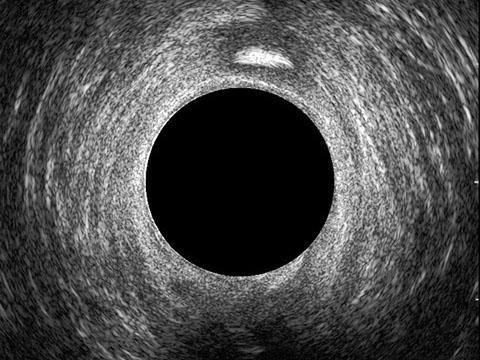

L’ecografia transanale è un esame diagnostico per immagini che consiste nell’introduzione di un trasduttore ad ultrasuoni. Le immagini qualitativamente migliori del canale anale sono ottenute usando un trasduttore rotante, montato in un manipolo rigido, che fornisce un’immagine a 360°. Con le apparecchiature più moderne è anche possibile ottenere immagini tridimensionali.

L’ecografia transanale permette di distinguere la sottomucosa che riveste il canale anale, lo sfintere anale interno, e lo sfintere anale esterno.